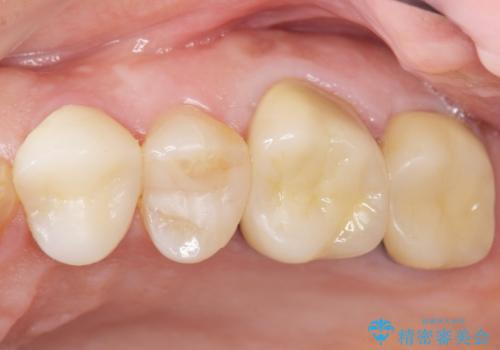

銀座しらゆり歯科の林院長による精密根管治療を受けて頂いたのち、メタルボンドクラウンによる補綴を行いました。

「今まで何回治療しても治らなった膿が出なくなった!」と喜んで下さいました。

クラウンの種類:メタルボンドクラウン エコノミー